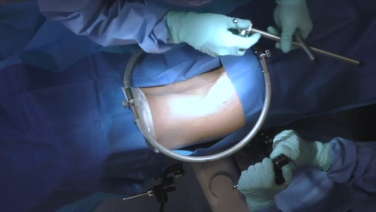

Anterior to the Psoas Surgical Demonstration with Joshua Herzog, MD

Single Position Anterior to Psoas Surgical Approach with Chi Lim, MD